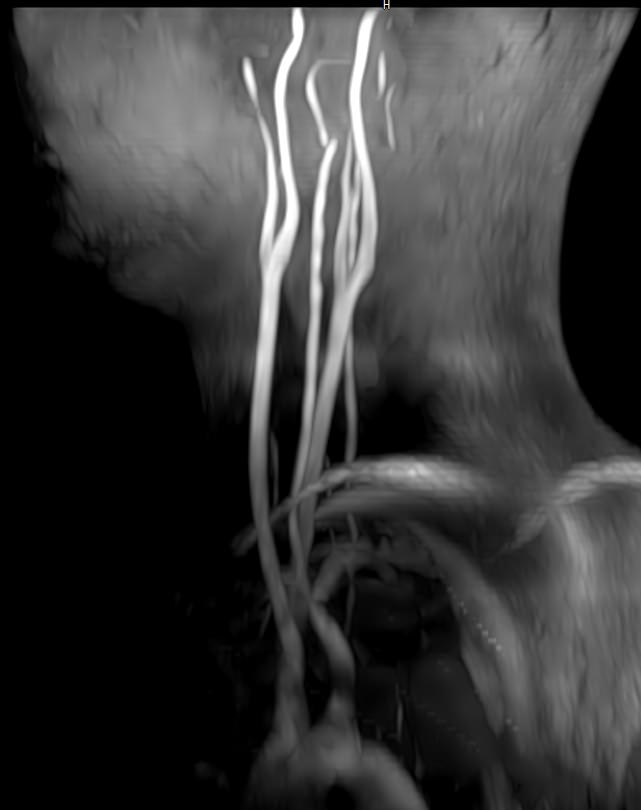

Кроме того, в области шеи проходят крупные кровеносные сосуды, кровоснабжающие все структуры головного мозга и мягких тканей головы. К ним относятся плечеголовной ствол, сонные и позвоночные артерии, которые далее в полости черепа соединяются между собой в Виллизиев круг. Это анатомическое образование позволяет компенсировать мозговой кровоток при патологических состояниях.

• участки сужения, извитость, образование петель и перегибов сосудов;

• нарушения оттока крови за счет тромбообразования в венозном русле;

• ангиомы, сосудистые мальформации;